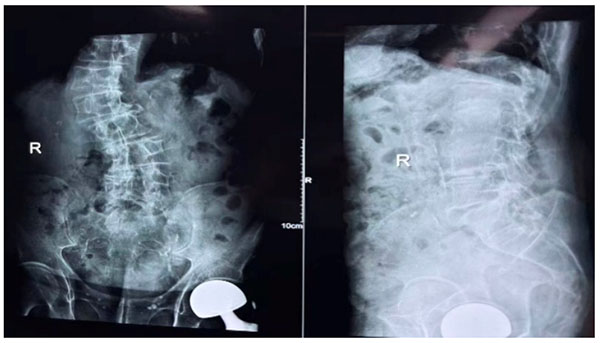

71岁的刘先生因腰椎退行性病变伴脊柱不稳入院,长期腰腿痛及活动受限严重影响生活质量。术前腰椎正侧位片提示病变节段椎间隙狭窄、脊柱序列异常,同时可见患者既往髋关节置换病史。考虑到患者高龄、基础情况复杂,我院骨外科团队经多学科会诊评估,最终选择OLIF+机器人辅助下椎弓根螺钉内固定术这一精准微创术式,在最大化稳定脊柱的同时,尽可能降低手术创伤。

术后即时正位+侧位X线片清晰显示:双侧椎弓根螺钉位置规整、钉道精准,连接棒锁定牢固,脊柱生理曲度得到有效维持,完美契合术前手术规划。内固定系统稳定,为患者术后早期康复奠定了坚实基础。